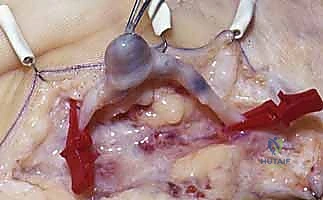

When excising a venous malformation or cavernous hemangioma, the lesion will appear as a spongy, purplish mass intimately intertwined with the surrounding fascia, tendon sheaths, or neurovascular bundles. Bipolar electrocautery is the instrument of choice; monopolar cautery risks thermal injury to adjacent nerves. The dissection proceeds circumferentially, utilizing a "peanut" sponge or fine tenotomy scissors to gently sweep normal tissue away from the pseudocapsule of the malformation. Feeding vessels are meticulously skeletonized, ligated with fine silk or metallic clips, and divided. If the malformation infiltrates a digital nerve (a common scenario), an operating microscope is brought into the field, and an epineurotomy is performed to dissect the vascular channels away from the nerve fascicles, accepting a subtotal resection if total excision would result in permanent anesthesia.

For subungual glomus tumors, the approach requires precision to prevent nail deformity. A digital block is performed, and a finger tourniquet is applied. The nail plate is carefully elevated and removed (or partially removed) using a Freer elevator. The sterile matrix is incised longitudinally directly over the bluish hue of the tumor. The tumor, typically a 2-5 mm encapsulated, pearl-like structure, is gently shelled out using a curette or fine iris scissors. It is imperative to inspect the bony floor of the distal phalanx for erosions and curette any residual cells. The nail bed is then meticulously repaired using 6-0 or 7-0 absorbable sutures (e.g., chromic gut) under magnification. The native nail plate, if intact, is fenestrated and replaced as a biological splint, tucked under the eponychial fold to prevent synechiae.